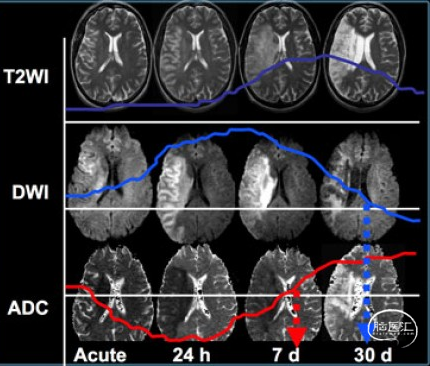

DWI影像改变:

超急性期(6h内)梗死区局部细胞毒性水肿,T2WI没有异常,DWI呈高信号,ADC呈低信号。

急性期(24h)细胞毒性水肿逐步向血管源性水肿转变,T2WI信号开始升高,DWI仍呈高信号,ADC呈低信号

亚急性期(7d)水肿进一步加重,T2WI上呈高信号,DWI仍呈高信号,ADC图上低信号逐渐上升。

慢性期(30d)脑组织坏死,T2WI和ADC图呈明显高信号,弥散不受限。

脑卒中急性期DWI、T2、ADC的影像表现如下: